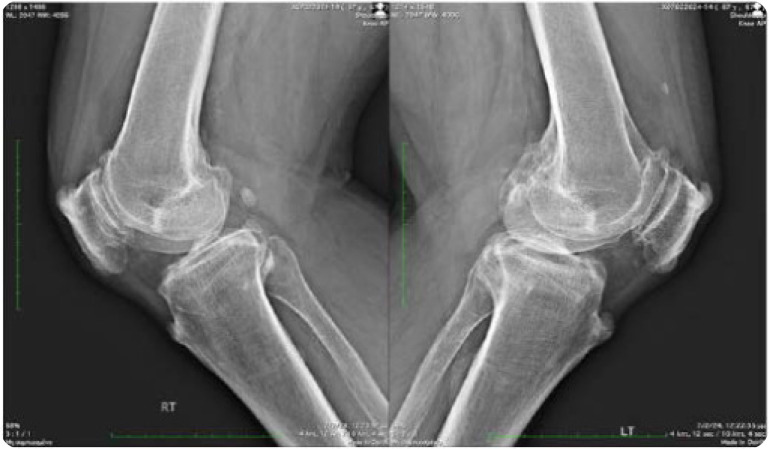

Diffuse Idiopathic Skeletal Hyperostosis, beyond the Axial Skeleton: Extra-spinal DISH.